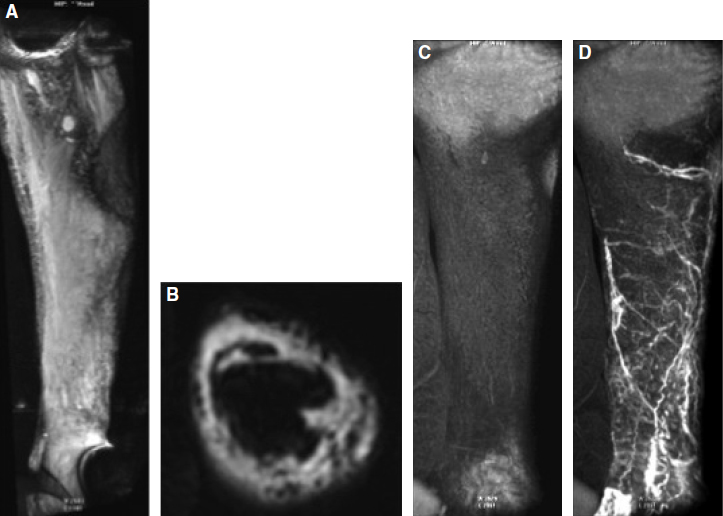

Alternatively, a dedicated peripheral vascular surface coil can be used to image the upper and lower legs simultaneously. 14 At 3.0 T we use a digital system that allows automatic coil element selection for the desired scan range, and the study is performed as a three-station examination. Because inhomogeneous fat suppression can produce regions of high signal that can obscure lymphatic channels and areas of dermal backflow 9 (Fig. 28-1), patient position with unilateral examinations is offset laterally to place the extremity of interest as close as possible to the magnet isocenter, which improves shimming and the uniformity of fat suppression.

Two primary sequences are included in our MRL examination: (1) a heavily T2-weighted three-dimensional turbo spin-echo with spectral fat suppression (spectral presaturation with inversion recovery) to define the severity and extent of edema and (2) a dynamic T1-weighted three-dimensional spoiled gradient–recalled echo (3D T1w GRE) with fat suppression before and after the intracutaneous contrast injection to visualize enhancing lymphatic channels and dermal backflow (Figs. 28-1 and 28-2). Example MR sequence parameters used at our institution are presented in Table 28-1.